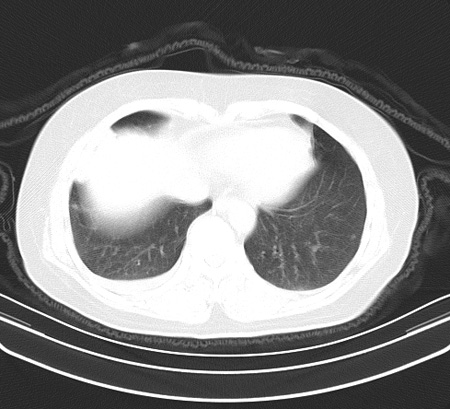

以下是引用余辉在2009-2-19 20:10:00的发言:[br]多考虑急性感染性病变,右中叶尚可见多枚小斑片状影,多为化脓性肺炎,双侧胸腔积液

以下是引用随光逐影在2009-2-19 20:33:00的发言:[br]1)考虑右肺炎症;建议抗炎治疗后复查。2)双侧胸腔积液(以右侧为甚)。

以下是引用花凤凰在2009-2-19 20:46:00的发言:[br]病人有发热,胸痛急性起病,主要病变位于右肺中叶外侧段,呈楔行改变,位于外带胸膜下,考虑为肺梗塞可能!!!!!!!!!!!!!!!!!!!!!!!!!!!!!!!!!!!